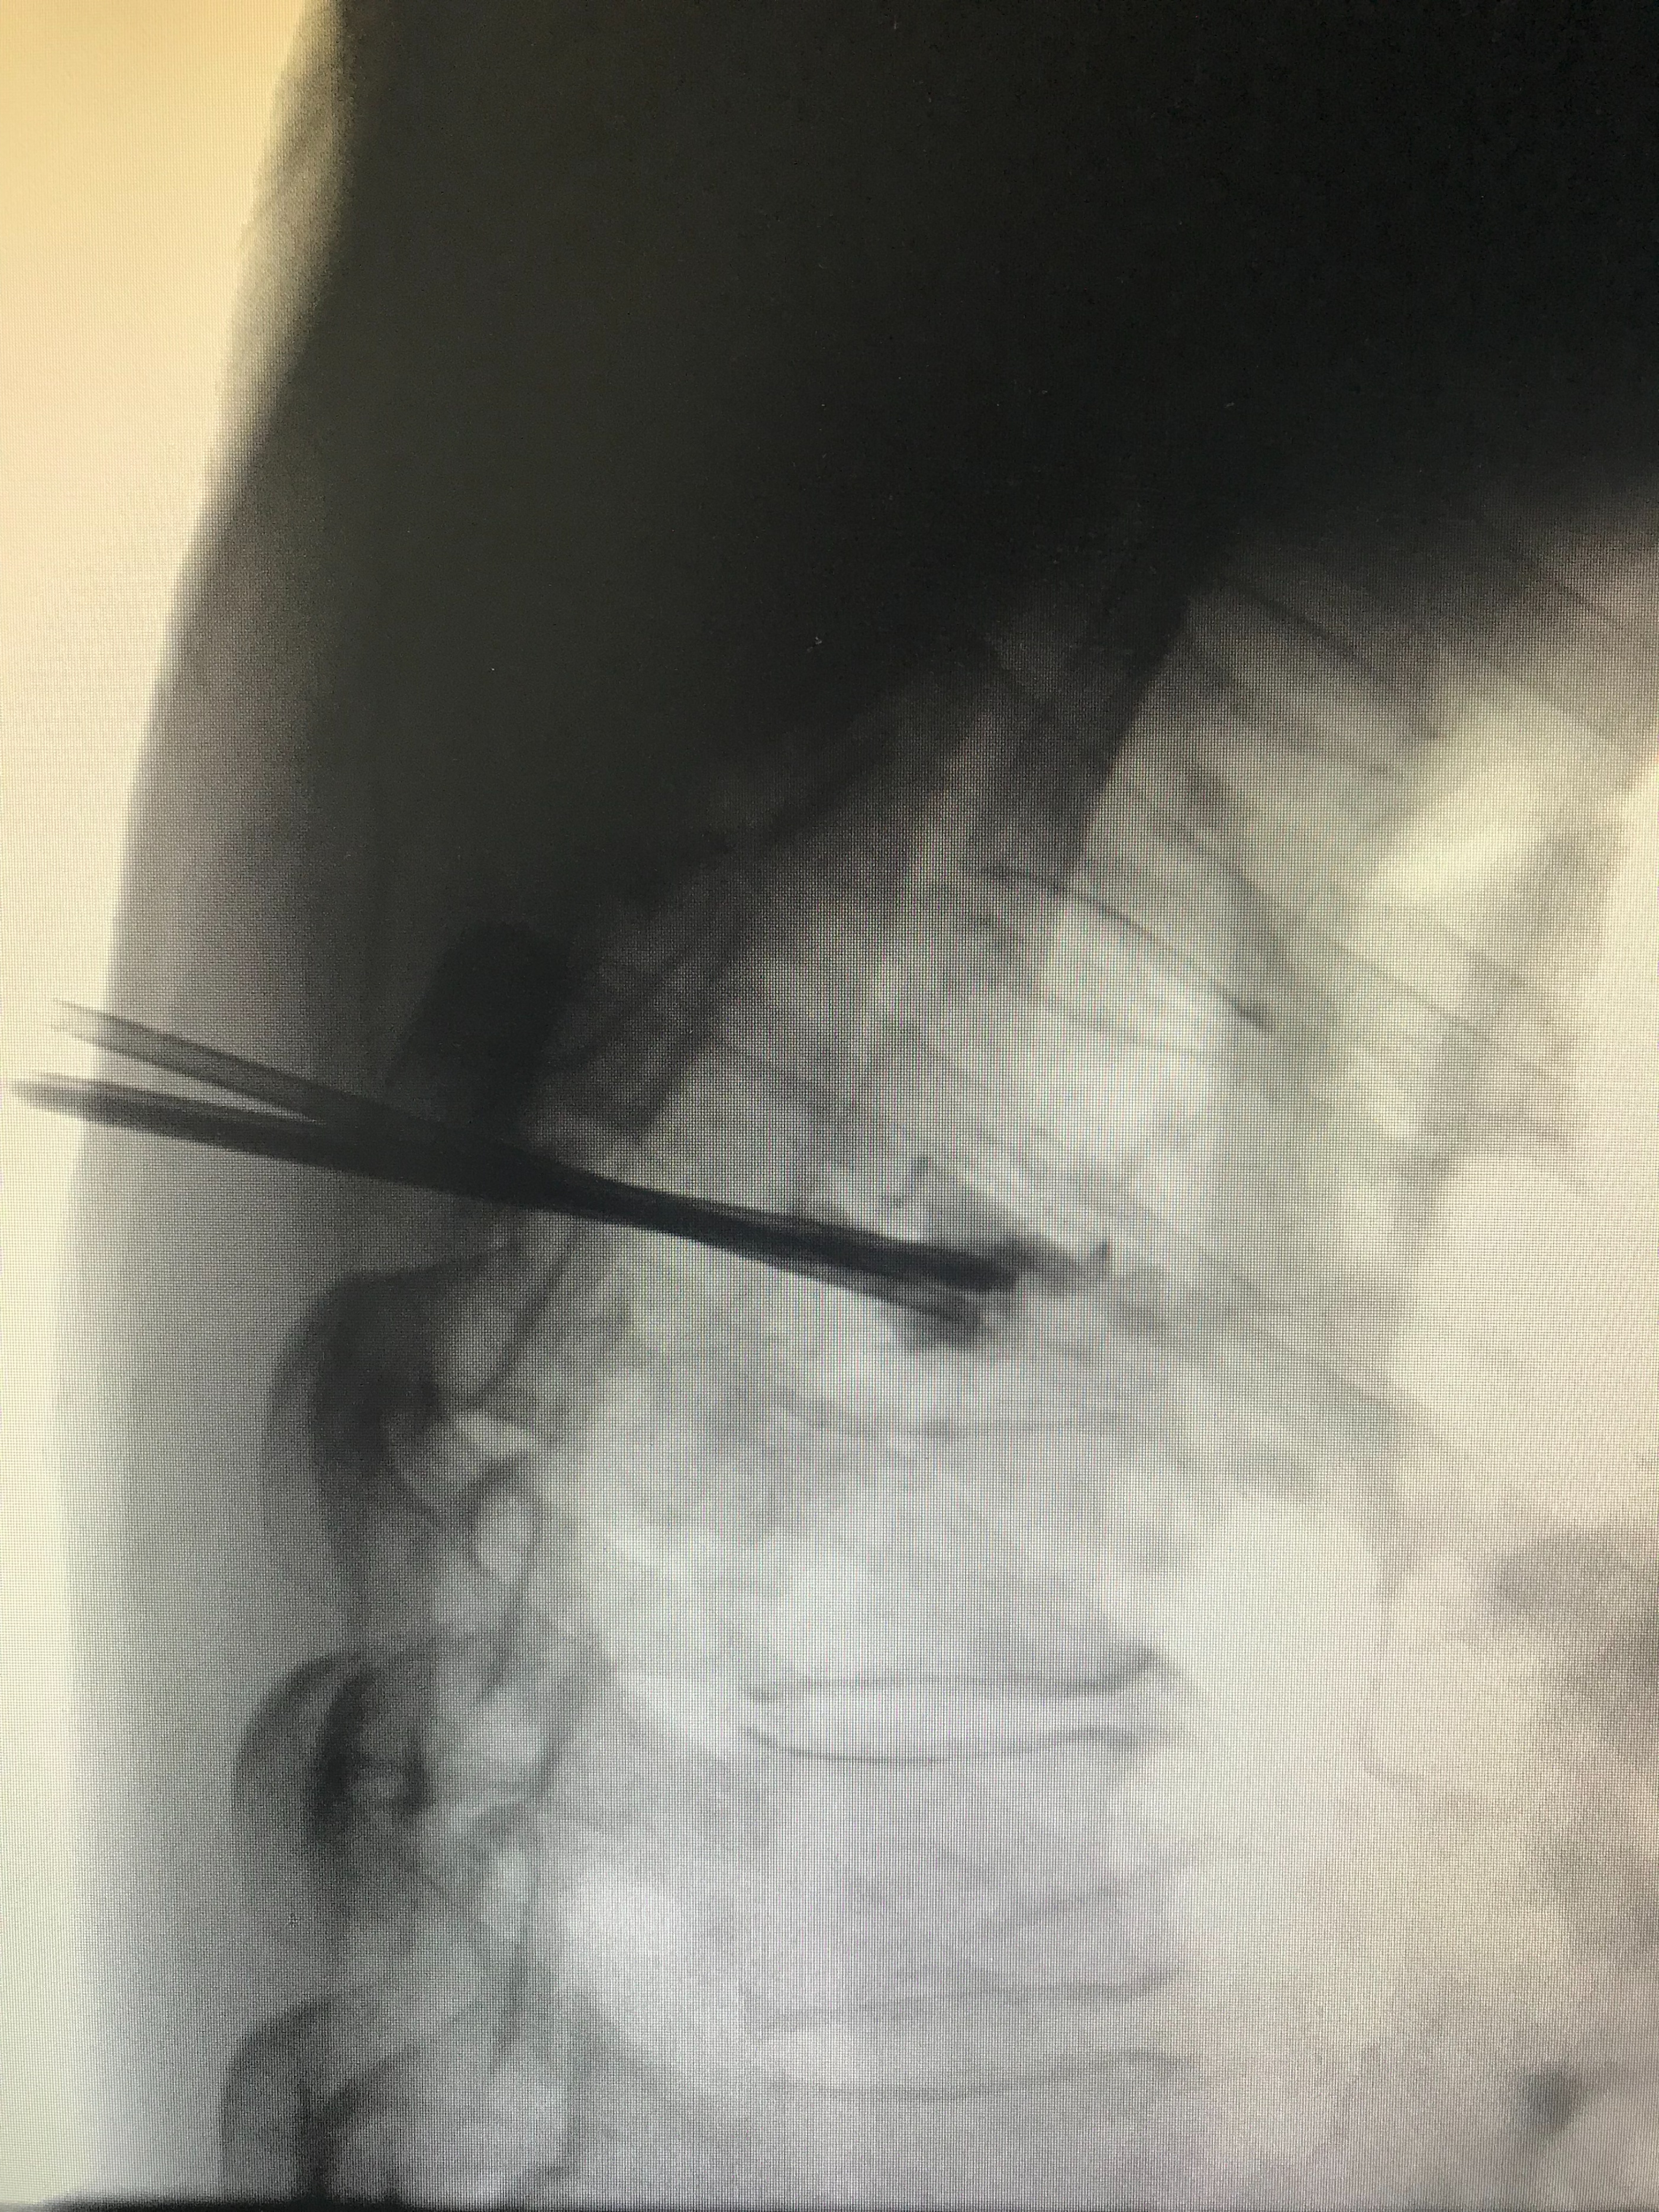

DSA引导下双侧椎弓根入路置针成功(侧位)

双侧入路成功置针至靶点后,首先进行单针35W、靶温度60℃射频消融椎体肿瘤10分钟。

单针射频消融椎体肿瘤(侧位)